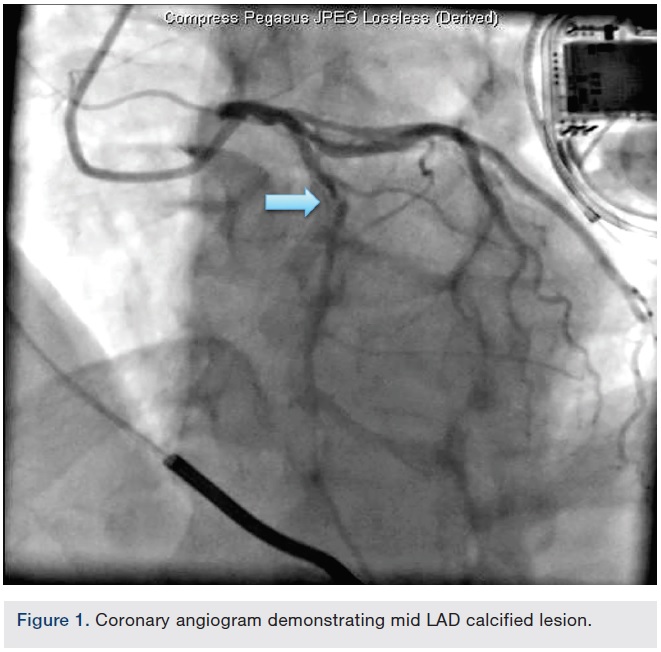

Gentle manual traction on the Rota burr shaft could not retract the burr, but did cause the vessel to accordion and caused the guide to deeply intubate the left main (LM) artery. Multiple attempts at spinning the burr were attempted, but it remained stalled. The patient remained hemodynamically stable.

Femoral access was obtained. The LM was engaged with a second guide (Xtra Backup [XB] 3.5 guide). A BMW wire was negotiated to the distal LAD beyond the burr. Multiple inflations of a 1.5 x 12 mm balloon were performed beside, proximal, and distal to the burr. This was followed by serial inflations using a 2.0 x 12 mm balloon. A slight tug on the Rota burr was then successful in retrieving it.